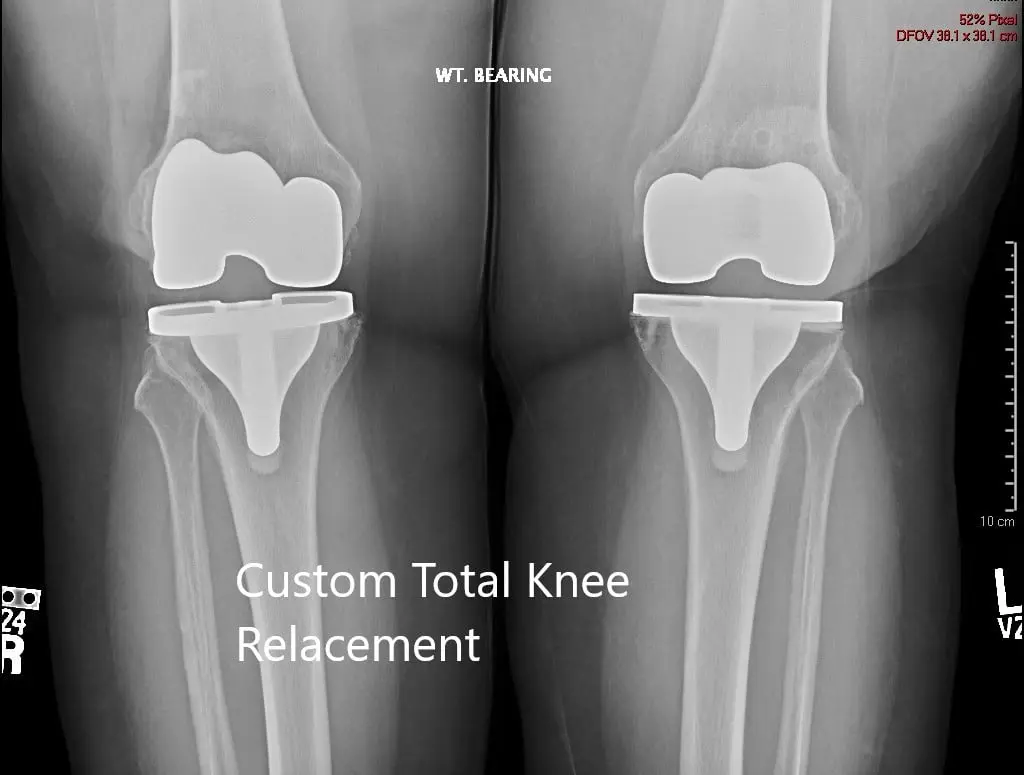

Postoperative X-ray showing the AP view of both knees

IMPLANTS USED: Customized knee replacement systems left and right. Bilateral polyethylene size 8 mm and patella size 32 mm x 6 mm.